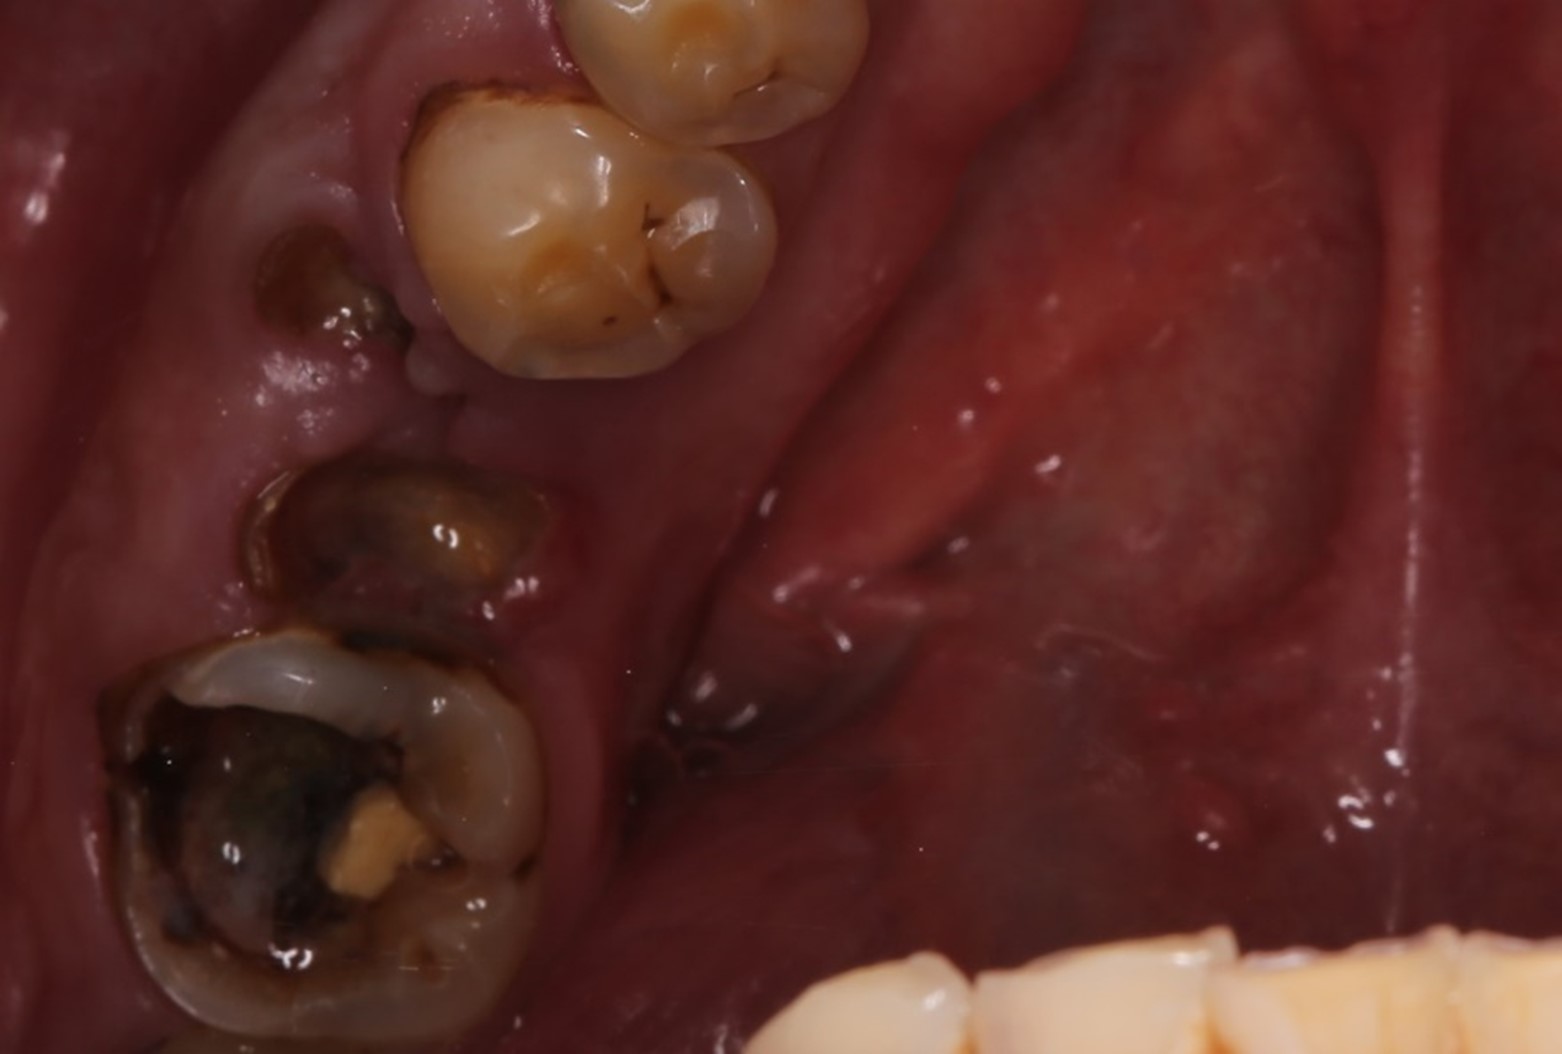

На нижней челюсти у него жевательных зубов не было вообще:

Особенно круто получилось с семёркой на нижней челюсти. Ярослав её пролечил, восстановил, и мы её спротезировали:

Такие разрушенные зубы, заросшие десной, кричат о необходимости имплантации